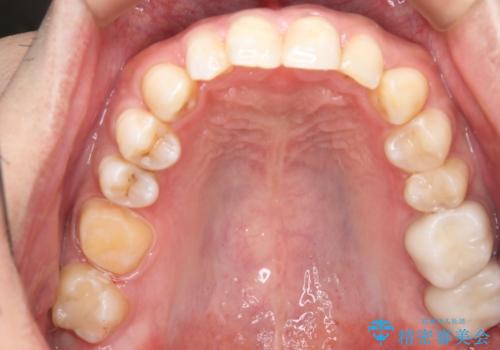

- 右上下6番の銀歯のやり変えを希望された患者様です。

切削量・形態を考慮し、上はセラミッククラウン、下はセラミックインレーでの治療を選択しました。

上はう蝕が歯頚部まで達していたのでクラウンでの治療を選択しました。

銀歯直下もう蝕が進行していたので全て除去した上でCRにて裏層しています。

下はクラウンほど切削量が多くないと判断し、インレーでの治療を選択しました。